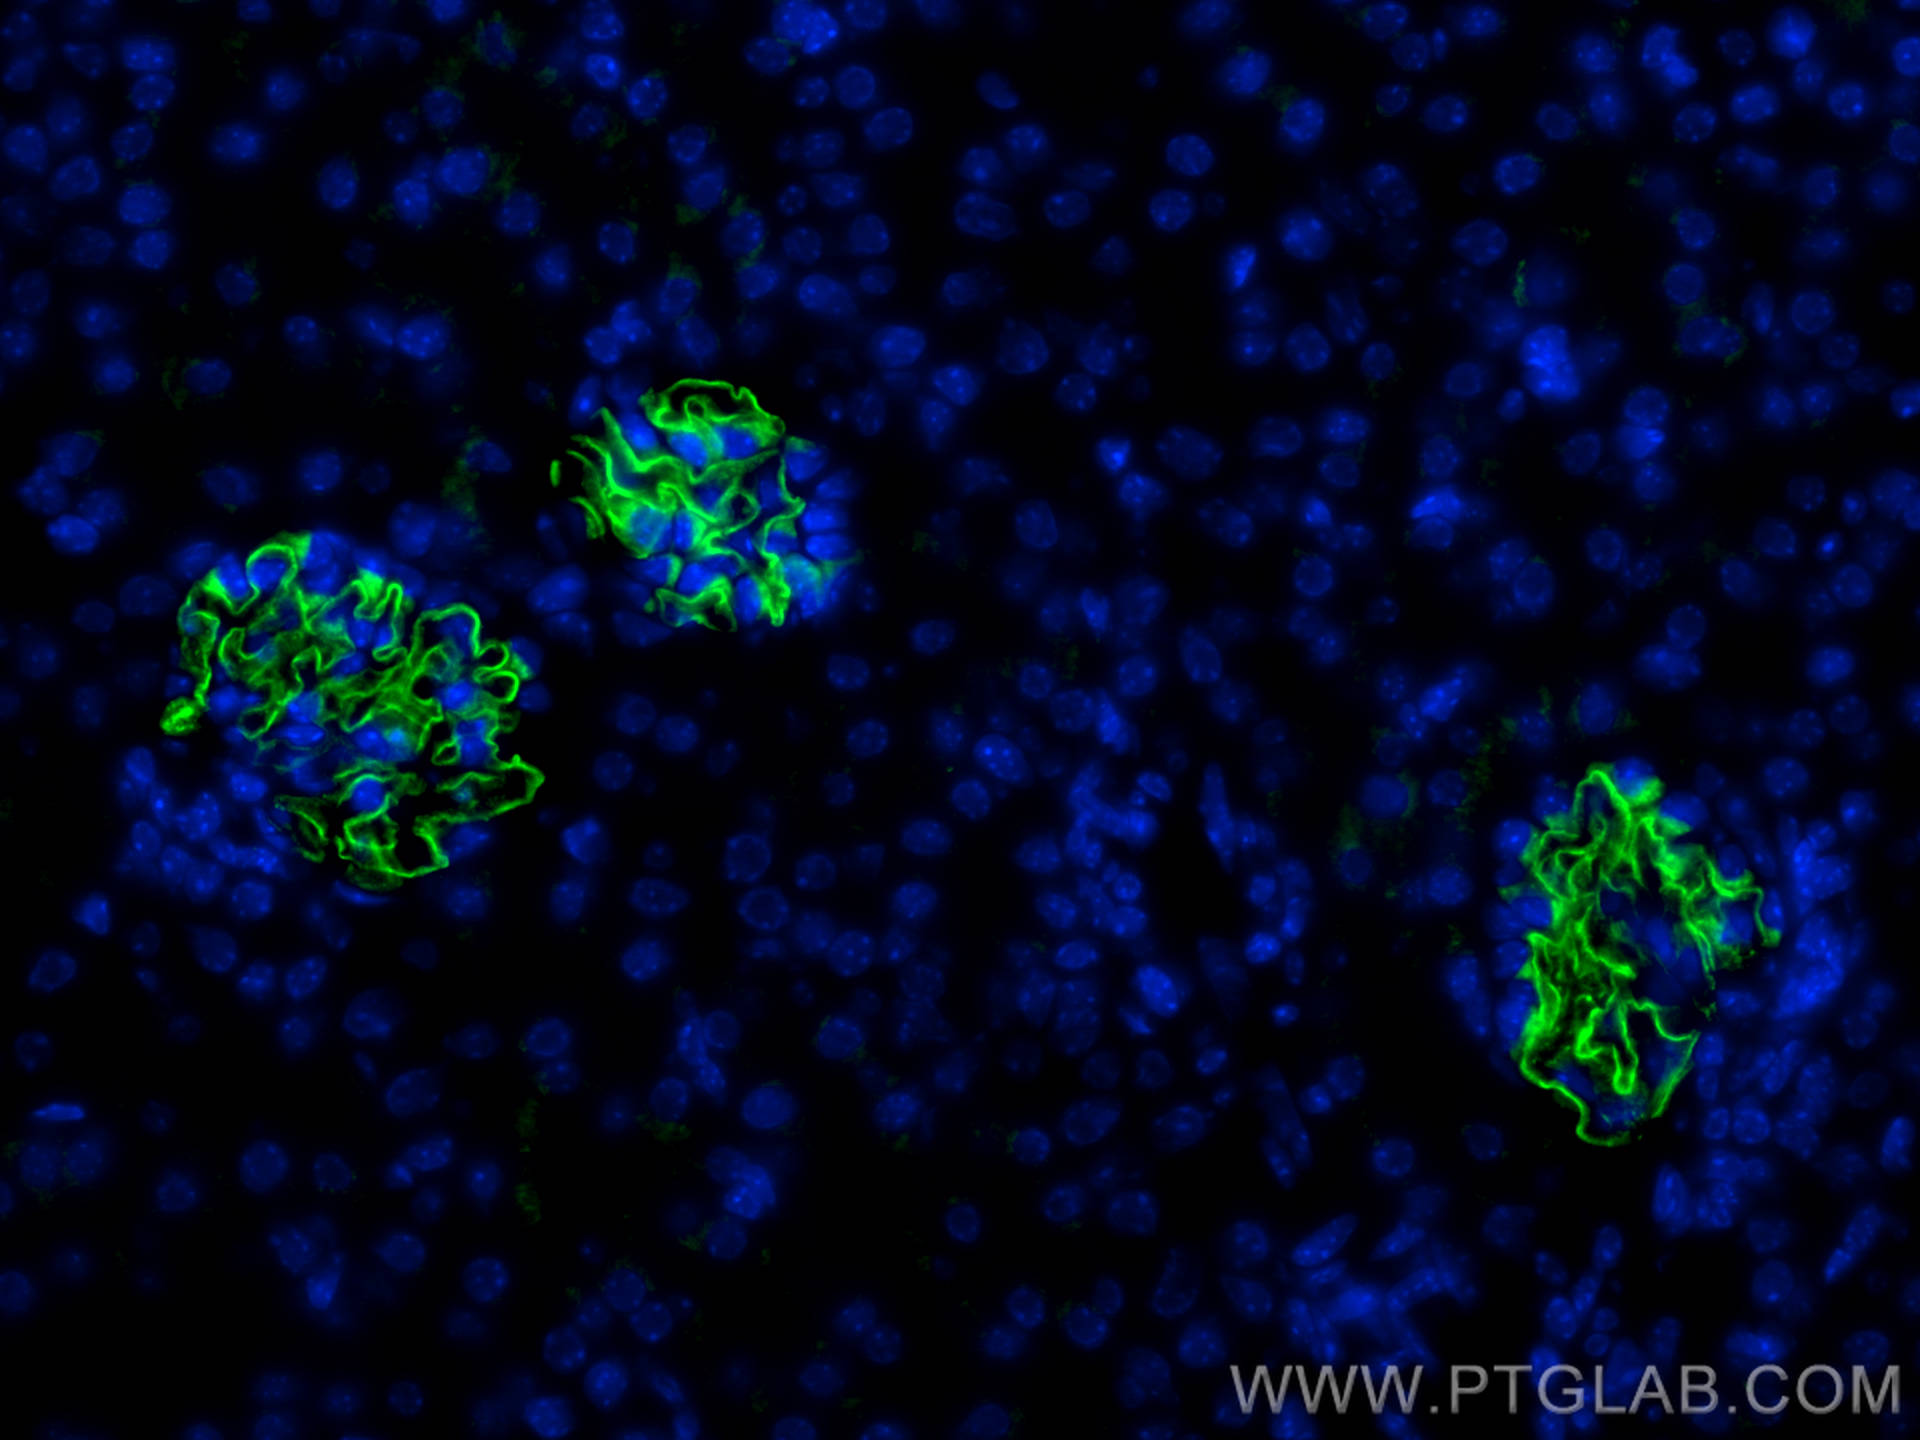

| Positive IF detected in | mouse kidney tissue, zebrafish embryos |